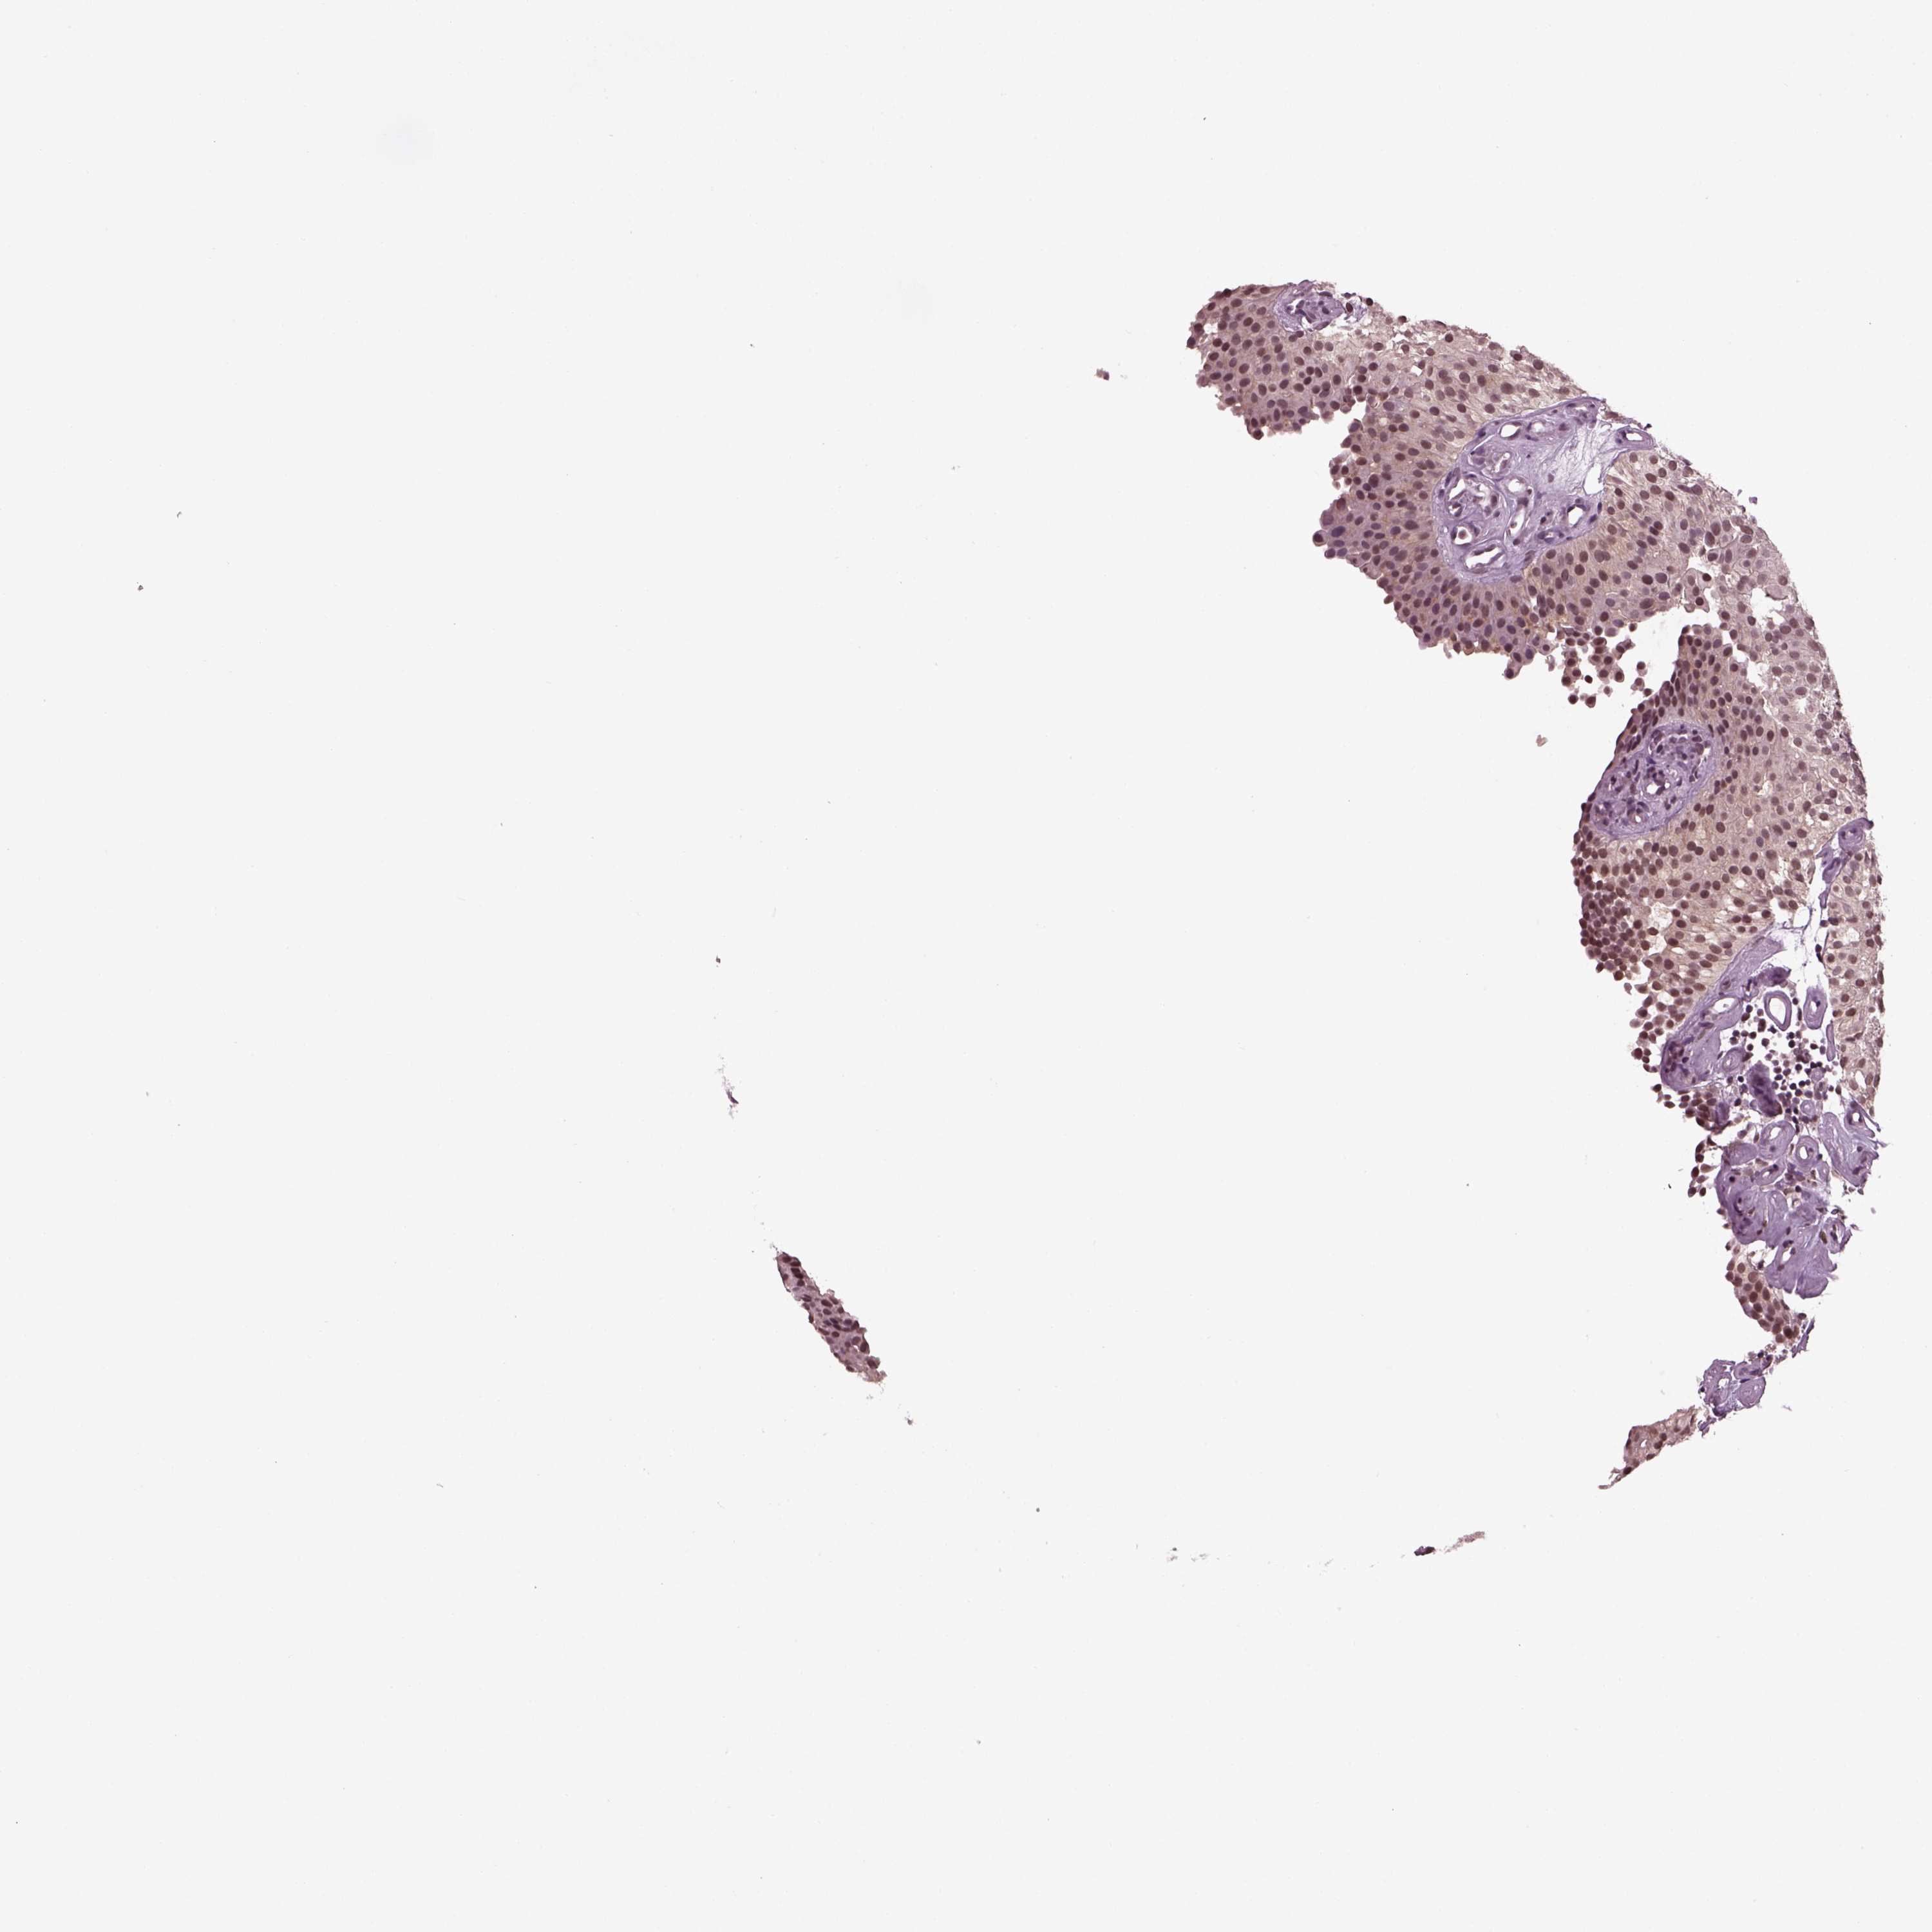

UROTHELIAL CANCER - Protein expressioni

A mouse-over function shows sample information and annotation data. Click on an image to view it in a full screen mode. Samples can be filtered based on level of antibody staining by selecting one or several of the following categories: high, medium, low and not detected. The assay and annotation is described here.

Note that samples used for immunohistochemistry by the Human Protein Atlas do not correspond to samples in the TCGA dataset.

Antibody stainingi

Antibody staining in the annotated cell types in the current human tissue is reported as not detected, low, medium, or high, based on conventional immunohistochemistry profiling in selected tissues. This score is based on the combination of the staining intensity and fraction of stained cells.

Each image is clickable and will lead to virtual microscopy that enables deeper exploration of all samples and also displays staining intensity scores, fraction scores and subcellular localization as well as patient and tissue information for each sample.

Antibody HPA067966

Antibody CAB012432

Staining

High

Medium

Low

Not detected

Intensity

Strong

Moderate

Weak

Negative

Quantity

>75%

75%-25%

<25%

None

Location

Nuclear

Cytoplasmic/membranous

Cytoplasmic/membranous,nuclear

Urothelial carcinoma, High grade

Urothelial carcinoma, NOS

Urothelial carcinoma, Low grade